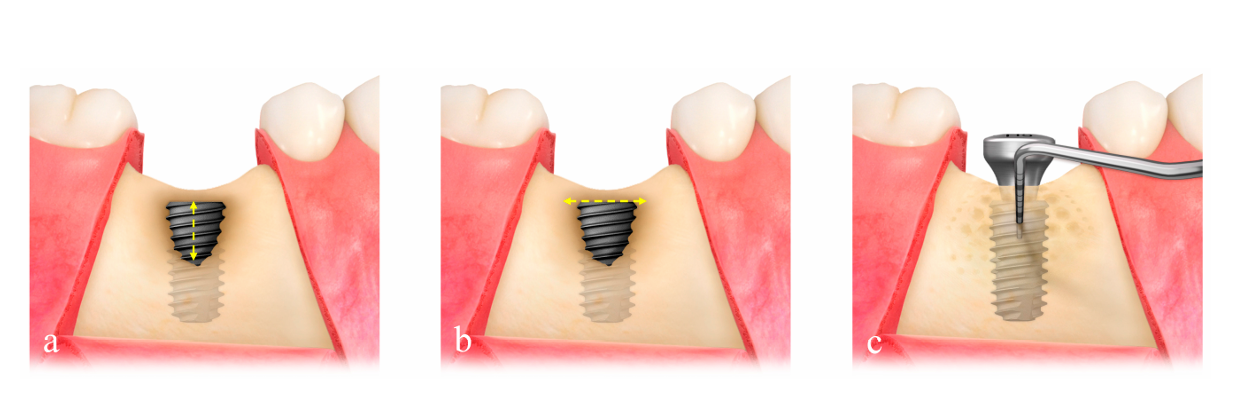

La dimensione del difetto (mm) consisteva in altezza del difetto, misurata dalla parte superiore dell'impianto al primo contatto osso-impianto, e larghezza del difetto, misurata dalla cresta ossea mesiale a quella distale a livello della parte superiore dell'impianto (Figura 2a,b). La rete di titanio ultrafine preformata (OssBuilder, Osstem), che era la più appropriata per la dimensione del difetto misurata, è stata selezionata da varie linee di tipo I per difetto di deiscenza buccale e tipo II per difetto di deiscenza bucco-prossimale combinato (Figura 3). Se necessario, sono stati effettuati piccoli ritocchi e modellamenti della rete di titanio per una migliore contenimento del materiale di innesto. Sono state eseguite più aperture del midollo osseo per indurre le cellule osteogeniche per una rigenerazione ossea più rapida e migliore.

Otto mesi dopo l'intervento, è stata eseguita una chirurgia di re-entry utilizzando un design di lembo simile sotto anestesia locale. Dopo la rimozione della rete di titanio, la densità ossea è stata valutata in base alla profondità di sondaggio, misurata nell'osso rigenerato sotto il centro medio della rete di titanio, utilizzando una forza controllata di 0,25 N (Figura 2c). Il cappuccio di copertura o il cappuccio di guarigione è stato sostituito da un abutment di guarigione, e i lembi sono stati regolati e suturati. I punti sono stati rimossi 10 giorni dopo l'intervento. Dopo la chirurgia di re-entry, il tessuto molle attorno all'abutment di guarigione è stato lasciato guarire prima della presa dell'impronta. Una singola restaurazione temporanea è stata incorporata con l'abutment personalizzato in titanio per un carico progressivo, e la restaurazione finale è stata consegnata 12 mesi dopo l'intervento. Eventuali sequel postoperatori nelle procedure GBR sono stati registrati secondo la precedente classificazione delle complicazioni GBR e trattati dallo stesso chirurgo (C.-J.P.).